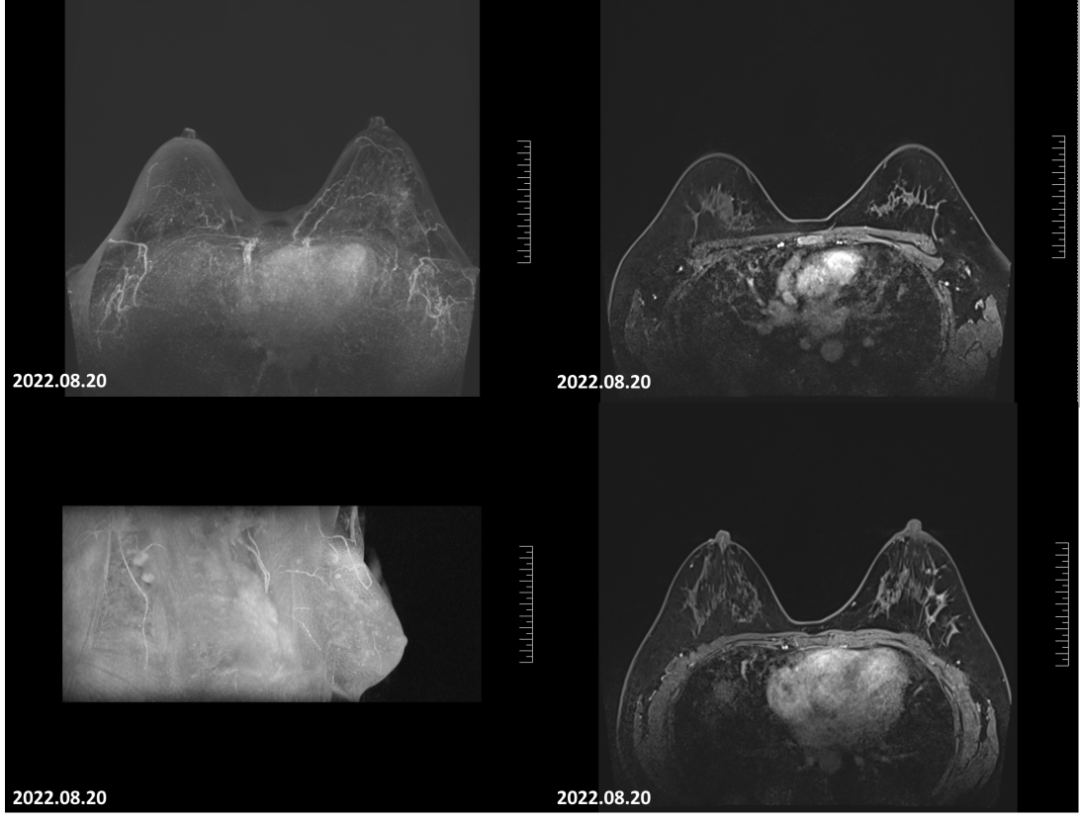

2022-05-20乳腺MRI报告:双侧乳腺欠对称,左乳较大,左乳皮肤局限增厚,左乳上方象限病变可见明显强化,边界不清,大小约46mm×73mm×52mm(上下径×左右径×前后径),病变前缘距乳头约17mm,后缘距离胸壁约8mm。左侧腋窝淋巴结肿大,最大直径约13mm。

图1.患者入院乳腺磁共振可见左乳肿瘤病灶范围广、累及皮肤,符合炎性乳腺癌表现。

2022-08-20乳腺MRI报告:左乳上方可见点灶状强化,以左乳约3点钟方向稍明显,直径约4mm。大小约24mm×30mm×21mm(上下径×左右径×前后径),病变前缘距乳头约34mm,后缘距离胸壁约11mm。左侧腋窝淋巴结肿大,最大直径约7mm。

图6.4疗程后患者左乳肿物轮廓不明显,左乳肿物及左腋窝淋巴结均无明显增强。

2022-08-20乳腺超声:左乳可见多处低回声结节,较大者位于12点钟,大小约11mm×7mm×11mm,距体表10mm,距乳头35mm,形态不规则,边缘成角,内回声不均匀。CDFI:内可及点状血流信号。左侧腋窝可见数个淋巴结回声,髓质消失,较大者大小约12mm×8mm。CDFI:内可见点状血流信号。右侧腋窝及双侧锁骨上窝未见明显肿大淋巴结。

图8 4疗程后,患者左乳肿物核心基本消失,淋巴结缩小至正常大小。